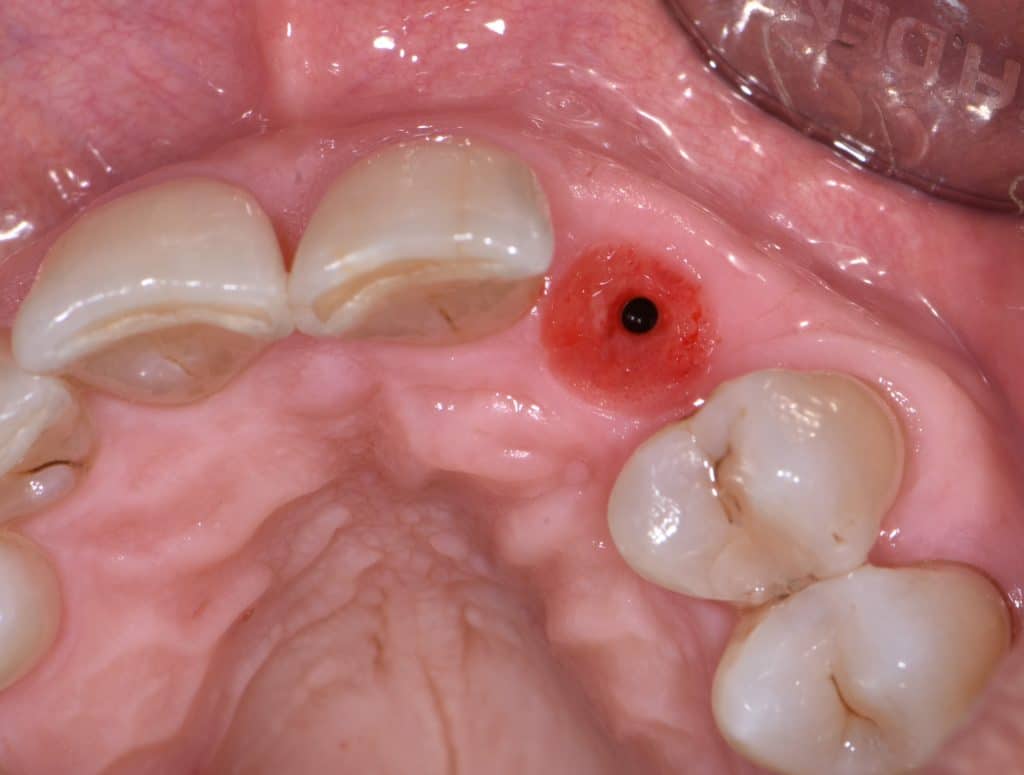

La pz N.G. di anni 52 (ASA 1) viene visitata nel mese di settembre 2017 per la mobilità ed inestetismo dell’elemento protesico 22, (foto iniziali sequenza 1) si evidenzia una frattura parziale della radice, si decide per l’estrazione ( foto sequenza 2) e sostituzione dell’elemento con un restauro implanto-protesico. Purtroppo la scarsa quota ossea apicale all’alveolo post-estrattivo (foto 2 rx) e l’alta valenza estetica dell’elemento ci rende cauti e si programma una socket preservation post estrattiva con l’ausilio delle membrane di prf (foto prf e socket sequenza 3 e 4). Durente i 5 mesi di guarigione la pz porta una protesi parziale mobile (foto 5,2) , a guarigione del sito post estrattivo si evidenzia una buona conservazione dei volumi osseo-gengivali,(foto guarigione sequenza 6) se pur presente una recessione distale all’elemnto 21.Nel mese di febbraio 2018 si procede all’inserimento di un impianto max-stability 3,75x12mm disegnando un lembo anticipato palatino per consentire un aumento dei tessuti vestibolari suturando con tecnica rool flap e trasformando l’elemento parziale mobile in una corona singola a carico immediato sul moncone temporameo applicando i concetti protesici bopt , (foto impianto moncone protesi provvisoria sequenza foto 7-8-9). Durante il periodo di maturazione dei tessuti molli vengono apportate opportune modifiche ai profili del provvisorio al fine di dare maggior spazio al tessuto gengivale, ( fotosequenza 10).Dopo circa 2 mesi dal protesizzazione provvisoria si è proceduto alla realizzazione del manufatto protesico con tecnica chair side sirona con l’ausilio del t-base (foto sequenza 11-12-13), realizzando in una sola seduta una corona in disilicato, ottenendo un risultato più che soddisfacente (Foto 14). Nel controllo a 3 mesi dal carico definitivo si apprezza la perfetta conservazione dei livelli ossei e gengivali. (foto sequenza 15).concludo con un follow up a 18 . Tengo a sottolineare che un caso come questo è stato conducibile con buoni risultati solo grazie alla piena fiducia della pz e alla sua massima motivazione e collaborazione. Ad oggi la pz sorride soddisfatta del risultato. E questo rappresenta la massima ricompensa di chi dedica tutto se stesso alla professione.